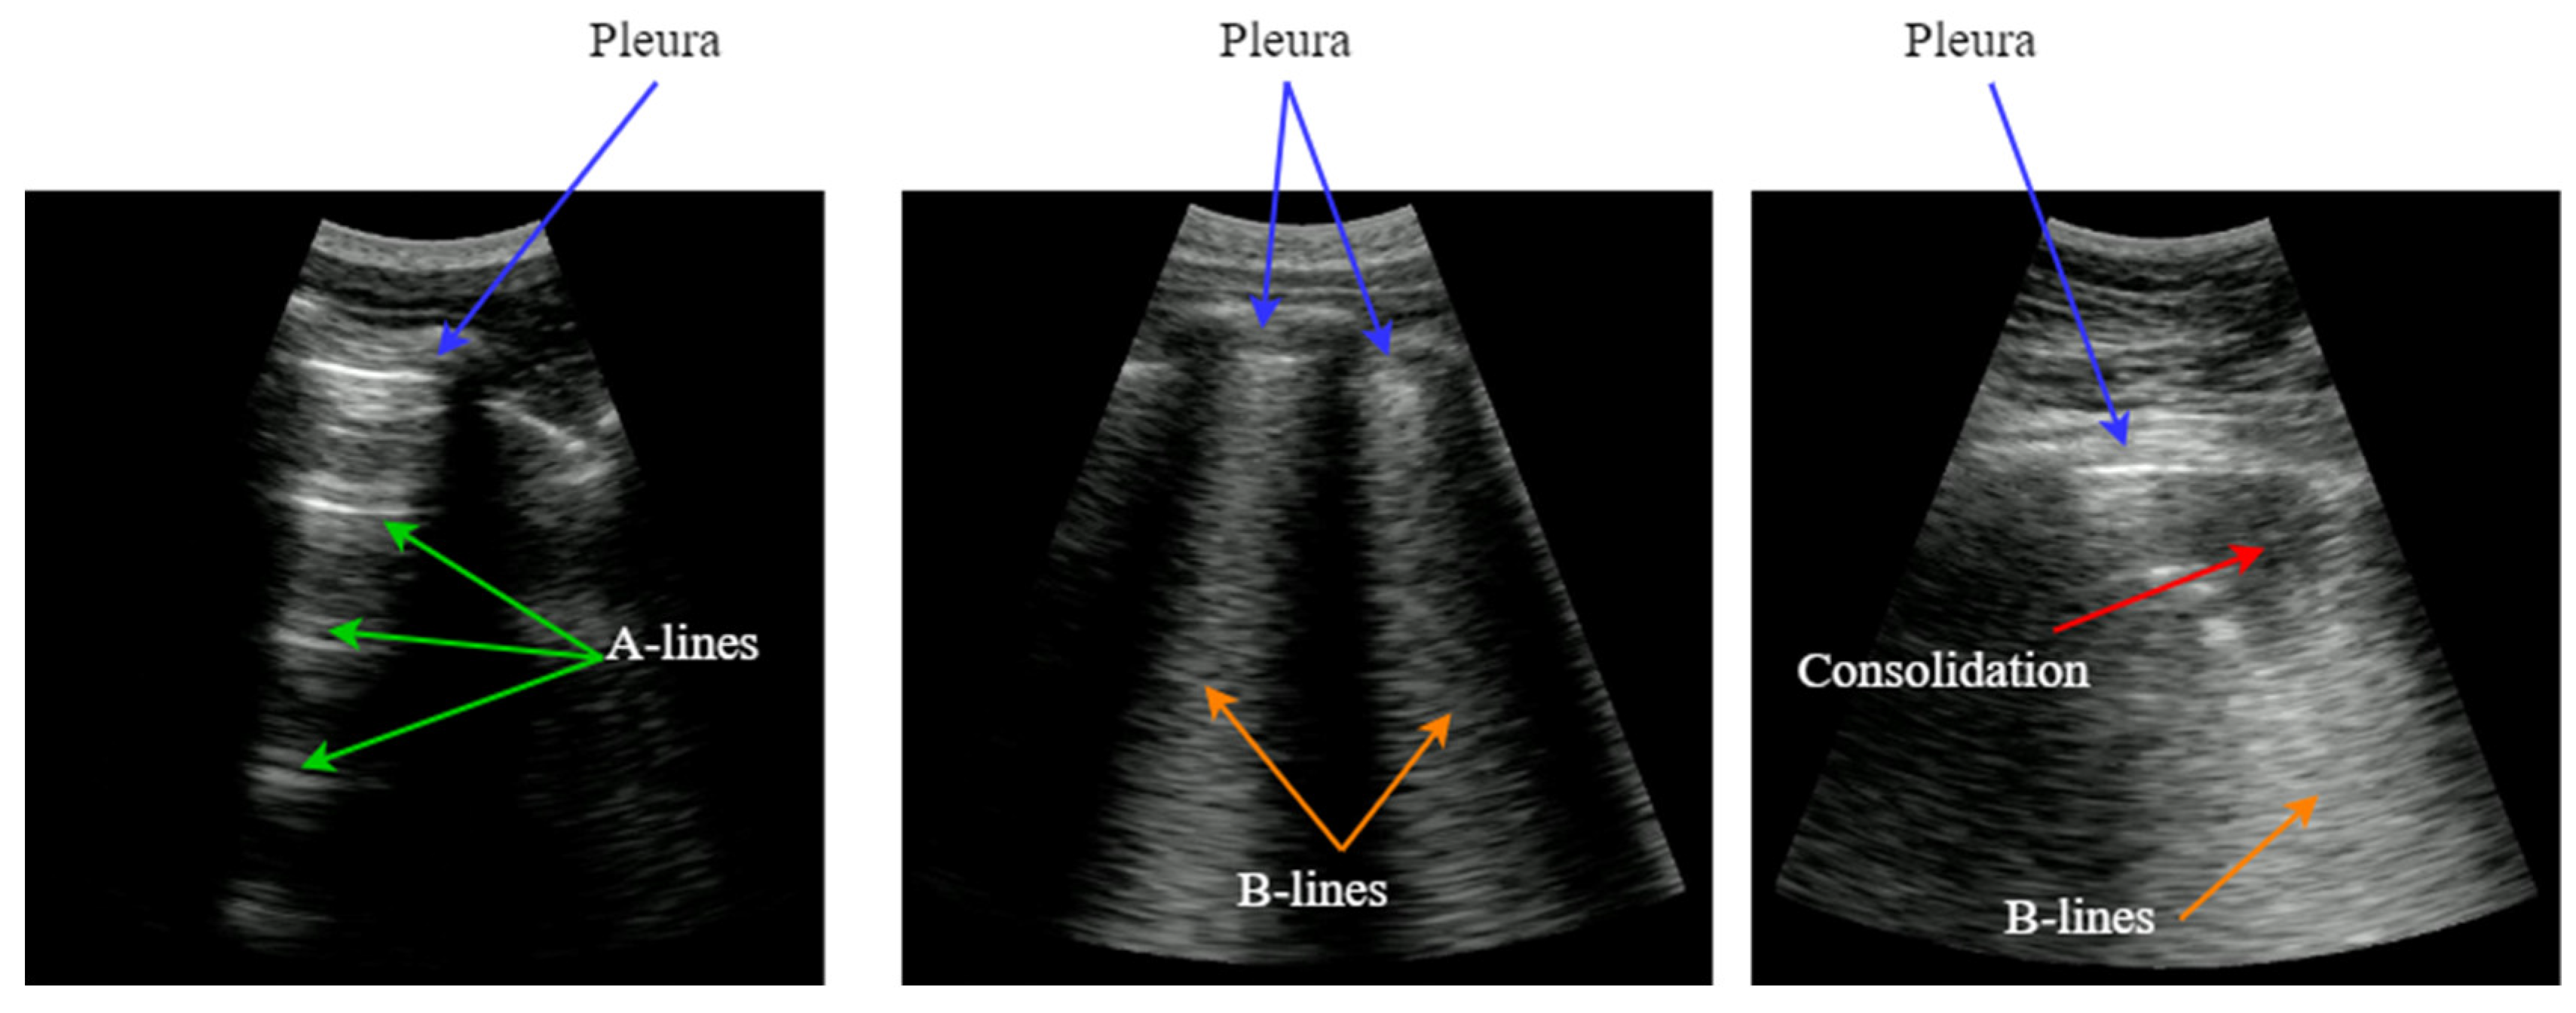

LUS images do not provide an anatomical view of the lung, because ultrasound waves hardly penetrate into the lung parenchyma because of the air presence in the alveoli. Instead, most of the acoustic energy is reflected by the pleura, which is the most easily identifiable structure, appearing like a bright horizontal line. Furthermore, replicas of the pleura appear at regular intervals below this line, generated by the reverberation of the incident wave between the transducer and the pleura. This artifact, named A-Line, is indicative of good lung condition.

In the presence of pneumonia and other interstitial syndrome diseases, the air inside the alveoli is progressively substituted by liquid, which modifies the acoustic impedance of the lung parenchyma, making it more similar to the impedance of muscle and fat above the pleura. As the acoustic impedance difference between both tissues reduces, more energy of the incident wave passes through the pleura to the lung parenchyma. But if air still remains in some alveoli, a local reverberation phenomenon occurs (acoustic trap), and a bright vertical line appears in the image because of the multiple echoes backscattered inside the lesion [3]. This vertical artifact is named B-Line, and it is indicative of the presence of pneumonia.

Figure 1. Typical LUS artifacts: Pleura (blue), A-lines (green), B-lines (orange), Consolidation (red).

Preprints 139804 g001

As the disease advances, more air is substituted by liquid and then consolidates into solid material. These consolidations appear in the image as hypoechoic regions, and constitute the third artifact usually looked for when imaging the lung. In sum, artifacts like A-lines, B-lines and consolidations, are indicative of the lung condition, and can be used to diagnose a pulmonary pathology [4]. Detecting and interpreting these artifacts is the key for a correct evaluation of lung images, which has been the principal bottleneck in the dissemination of this technique.